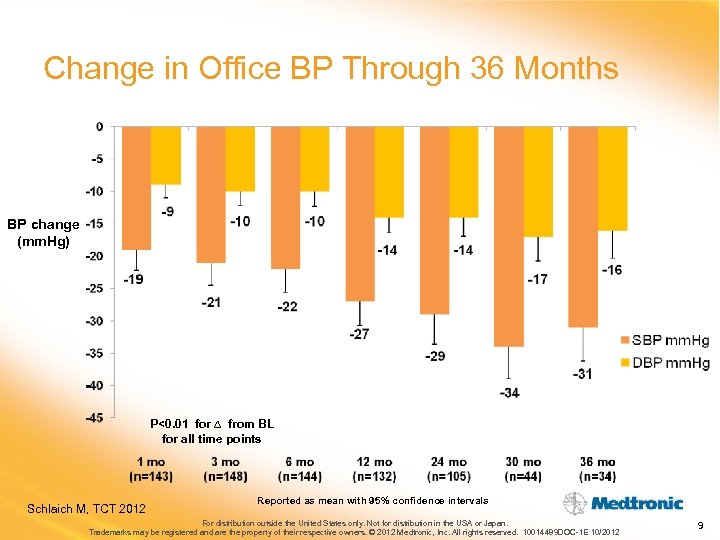

Change in Office BP Through 36 Months BP change (mm. Hg) P<0. 01 for ∆ from BL for all time points Schlaich M, TCT 2012 Reported as mean with 95% confidence intervals For distribution outside the United States only. Not for distribution in the USA or Japan. Trademarks may be registered and are the property of their respective owners. © 2012 Medtronic, Inc. All rights reserved. 10014489 DOC-1 E 10/2012 9

Change in Office BP Through 36 Months BP change (mm. Hg) P<0. 01 for ∆ from BL for all time points Schlaich M, TCT 2012 Reported as mean with 95% confidence intervals For distribution outside the United States only. Not for distribution in the USA or Japan. Trademarks may be registered and are the property of their respective owners. © 2012 Medtronic, Inc. All rights reserved. 10014489 DOC-1 E 10/2012 9